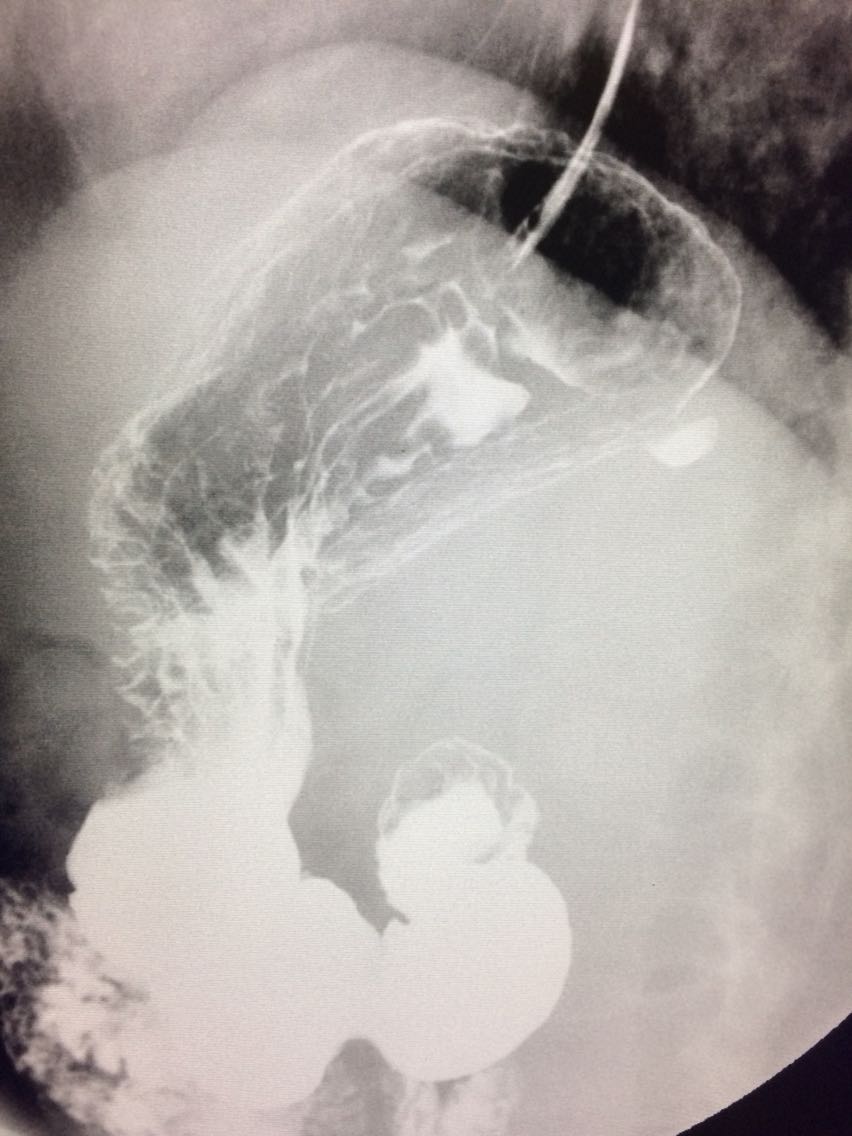

胃底憩室一例

女.47岁 体检来诊。 平素体健,无明显症状。 做上消化道造影如图。

诊断,胃底憩室。 治疗,患者无明显症状,未予治疗。